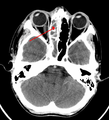

![]() | |

يشير السهم إلى منطقة الالتهاب في جيوب الفك العلوي في الجانب الأيسر من الوجه. لاحظ أن المنطقة التى يشير لها السهم ليست شفافه لقلة الهواء فيها، مما يشير إلى امتلائها بالسوائل بالمقارنه مع الجانب الآخر من الوجه. | |